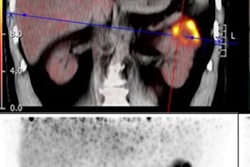

While multiple myeloma prognosis has been studied through clinical parameters, there's been a lack of data on how dual imaging modalities and multiple algorithms can further improve prognosis estimation in patients, according to the researchers. Using F-18 FDG-PET/CT-based radiomics, the Zhong team used data from 98 multiple myeloma patients to develop and test a number of models for predicting multiple myeloma prognosis.

The models incorporated different combinations of PET, CT, clinical parameters, and one of six types of machine-learning algorithms: Cox, gradient boosted-Cox, CoxBoost, a generalized boosted model, random forest survival, and support vector classification regression.

The final models all utilized five PET-based features, four CT-based features, and six clinically derived features that were all significantly related to progression-free survival. Following this, the team validated the resulting radiomics models using the bootstrap method for repeated resampling of data samples to generate larger sample sets.